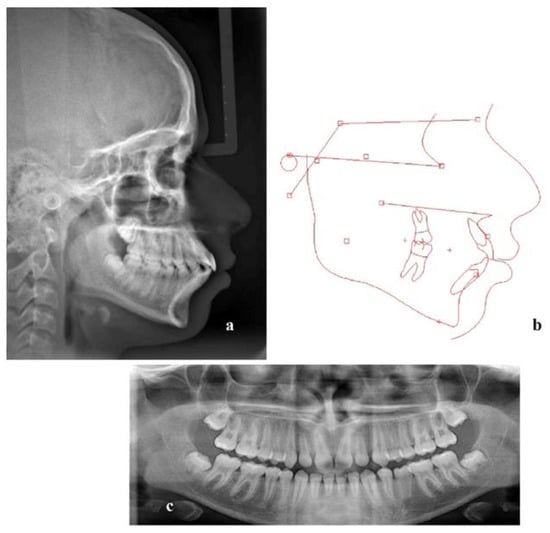

2. Materials and Methods

3. Results

| Measurement | Mean ± SD | Pretreatment | Posttreatment |

|---|---|---|---|

| 1. SNA (°) | 81 ± 3 | 88.1 | 89 |

| 2. SNB (°) | 78 ± 3 | 83 | 84.2 |

| 3. ANB (°) | 3 ± 2 | 5.1 | 4.9 |

| 4. Wits (mm) | 1 ± 2.9 | 0.1 | 0.8 |

| 5. GoGN/SN (°) | 32.5 ± 5.2 | 27.1 | 25.8 |

| 6. U1/PP (°) | 109 ± 6 | 125.9 | 117.1 |

| 7. L1/MP (°) | 93 ± 6 | 110.8 | 94.5 |

| 8. Interincisal angle (°) | 135 ± 10 | 104.6 | 130.2 |

| 9. Labionasal angle (°) | 95.96 ± 2.57 | 106.6 | 99 |